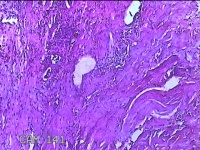

右侧食指远端结节

性别

男

年龄

47岁

临床诊断

皮下结节

一般病史

发现右侧食指3天。

标本名称

大体所见

灰白暗红色带皮肤样结节1.2x0.7x0.3cm一个,表面糜烂,切面灰白粉红色,质中。